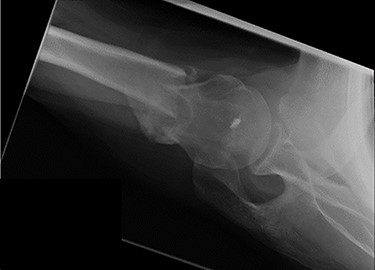

Review at 6 weeks post-injury demonstrated both clinical and radiological healing (Fig. 7). At a final 14-week review, the patient informed that he had returned to playing golf with no adverse symptoms. Examination revealed complete soft tissue healing over the fracture site and the range of movement was recorded as 120° of both abduction and forward flexion. Plain radiographs confirmed excellent fracture union, and the patient was discharged (Fig. 8).

Axial view X-ray taken 14 weeks post-injury showing excellent fracture union and articulation between the humeral head and glenoid.